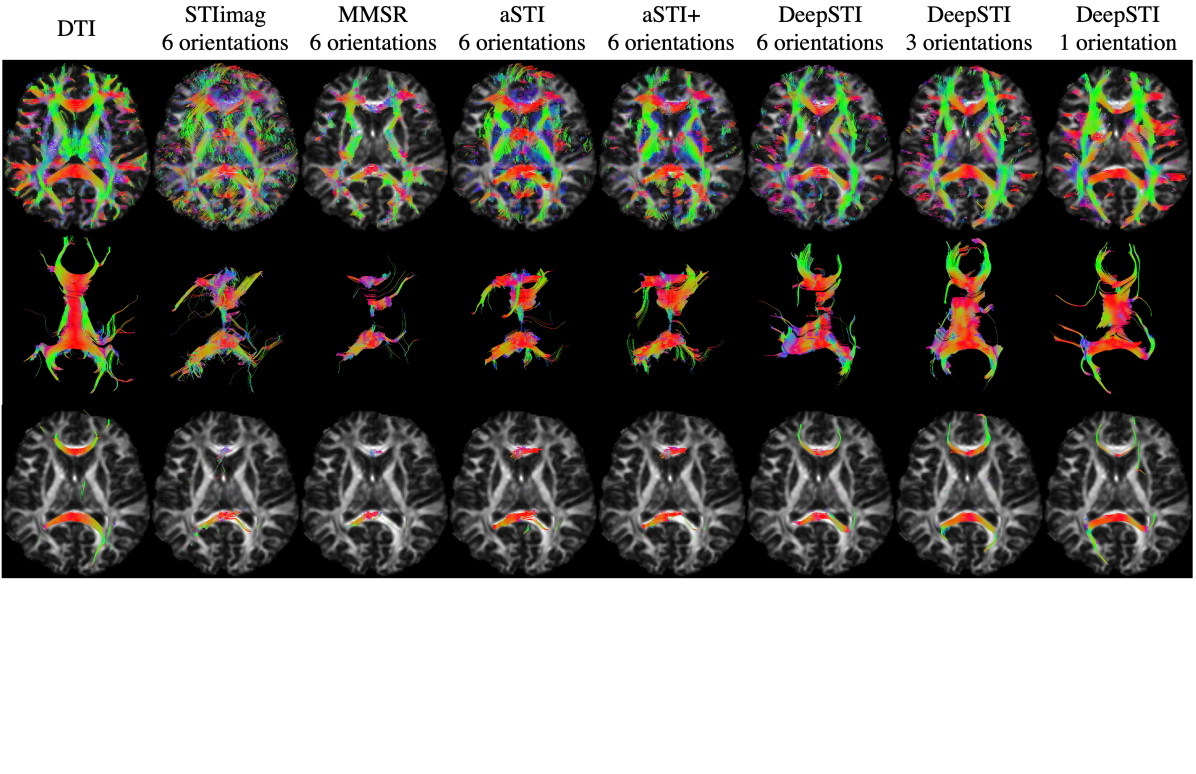

Refer to caption

Figure 5: STI-based Fiber tractography results from phase measurements for a subject at 7T with 0.98×\times0.98×1(mm)3absent1superscript𝑚𝑚3\times 1(mm)^{3} resolution. Rows 1-3: whole brain tracking results overlaid on a DTI-based FA map at different axial planes. Row 4: 3D volume rendering of neural fibers passing corpus callosum. Row 5: 2D visualization of neural fibers passing corpus callosum. Columns from left to right: DTI, STIimag’s result from 4 orientations, MMSR’s result from 4 orientations, aSTI’s result from 4 orientations, aSTI+’s result from 4 orientations, DeepSTI’s results from 4, 3, 2 and 1 orientations. No FA or MSA weighting is used in visualizing the tractography results.

Figure 5 depicts fiber tracking results achieved by different methods using in vivo data acquired at 7T with 0.98×\times0.98×\times1 mm resolution. With 4 head orientations, DeepSTI provides more complete fiber reconstructions as compared to other STI methods. Even with fewer head orientations, DeepSTI can still recover a good portion of major fiber pathways in whole brain tracking (top row of Fig. 5). Notably, the fibers passing through CC connecting the left and right hemispheres can still be nicely recovered even from only one head orientation (middle and bottom rows of Fig. 5). Results for a 3T subject are included in the Appendix (Fig. 11).

Figure 6: Tracking of callosal fiber bundle that connects the occipital lobes via the splenium of corpus callosum (forceps major) from measurements of a subject at 7T with 0.98×\times0.98×1(mm)3absent1superscript𝑚𝑚3\times 1(mm)^{3} resolution. From left to right: reference DTI reconstruction (acquired at 2.2 mm isotropic resolution and interpolated to 0.98×\times0.98×1(mm)3absent1superscript𝑚𝑚3\times 1(mm)^{3} resolution), STI reconstruction from STIimag using four orientations, STI reconstruction from DeepSTI using four orientations. Note that MMSR, aSTI and aSTI+ did not recover any tracts that satisfy the anatomical constraint of the forceps major.

Fig. 6 depicts tractography results for the forceps major using the same 7T dataset as in Fig. 5. In this task, most existing STI methods (including MMSR, aSTI and aSTI+) failed to reconstruct the forceps major, yielding no tracts that satisfy the given anatomical constraint. STIimag was able to produce a small portion of tracts, but largely incomplete. DeepSTI yielded the most coherent and complete result among all STI methods, with a complete C-shape structure.